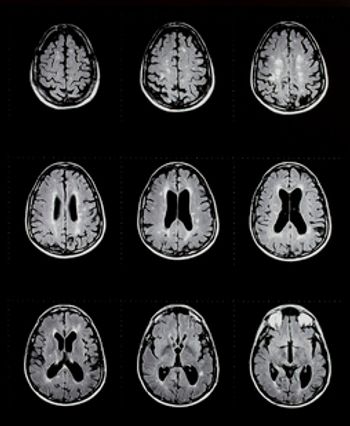

Cortical lesions play a major role in the progression of multiple sclerosis (MS). A recent study looked to longitudinally characterize the development and evolution of cortical lesions in MS across the cortical width, as well as their relationship with white matter lesion accrual.